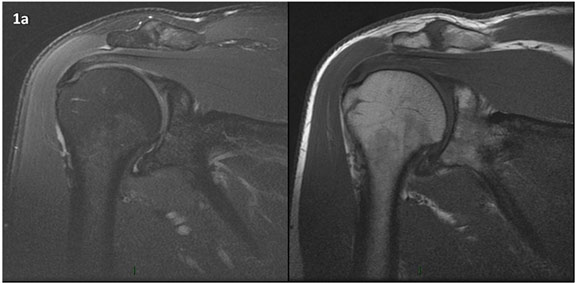

Figura 1 (a-g): Imagens consecutivas de RM no plano coronal nas ponderações DP com supressão de gordura (DP SG) à esquerda e T1 à direita. Clique na seta para passar as imagens.

Figura 1a’ mostrando rotura parcial articular na inserção do supraespinhal (setas azuis).

Figuras 1b’ a 1g’ mostrando atrofia da porção superior do músculo redondo menor (seta salmão), com lipossubstituição mais evidente das mais fibras laterais (seta amarela). As fibras mais inferiores e mediais têm atrofia menos evidente.

Repare que estas alterações não são evidentes nas imagens com supressão de gordura.